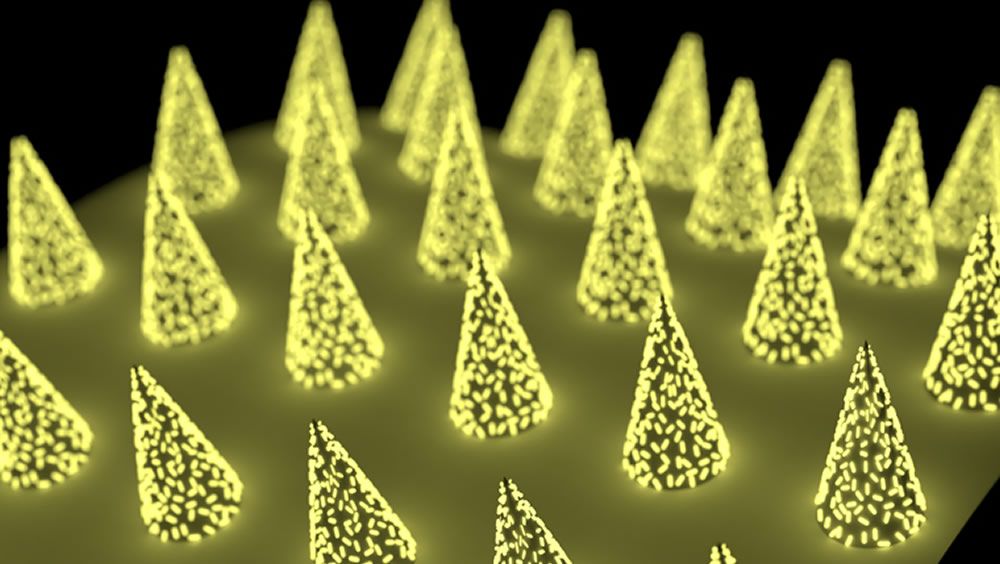

Investigadores de la Universidad de Washington han desarrollado un parche de microagujas que puede ayudar a detectar pequeñas cantidades de anticuerpos en el líquido intersticial.

La nueva tecnología supera un cuello de botella con muchos sistemas de parche de microagujas: su poca sensibilidad. Los investigadores utilizaron “plasmónicos-flúores”, nanoetiquetas fluorescentes, para detectar biomarcadores de proteínas presentes en pequeñas cantidades en el líquido intersticial.

Los parches de microagujas, donde se aplica un parche tachonado de pequeñas agujas en la piel para obtener una muestra del líquido intersticial que reside entre nuestras células, ofrecen una alternativa fácil e indolora.

Sin embargo, los biomarcadores de proteínas, como los anticuerpos, suelen estar presentes en concentraciones bajas en el líquido intersticial, lo que dificulta su detección en muestras derivadas de microagujas. Hasta la fecha, esto ha sido un cuello de botella para la tecnología de microagujas.

Este nuevo sistema utiliza plasmónicos-flúores para potenciar la detección de proteínas presentes en niveles muy bajos. La señal de los biomarcadores diana en las muestras fue aproximadamente 1.400 veces más brillante que la de los marcadores fluorescentes convencionales.